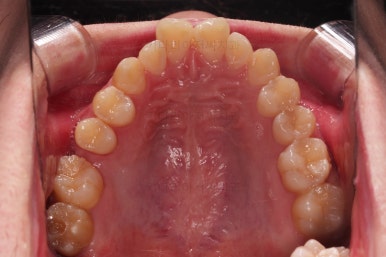

초진 시 X-ray 사진입니다.

위쪽 어금니 하나가 없는 걸 볼 수 있는데요.

다행히 해당 부위는 맨뒤에 사랑니까지 남아있던 상황이었어요. 환자분이 혹시나 하는 마음에 해당 부위 사랑니는 발치를 안하고 아껴두셨던거죠.

부산교정치과 초진 시 입안의 모습입니다.